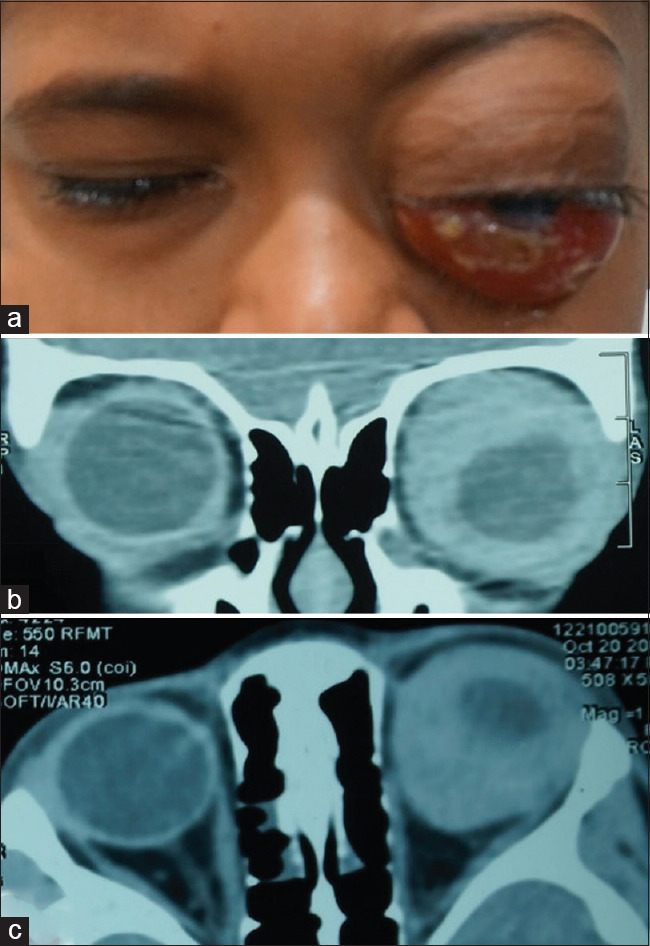

A 5-year-old boy presented with gradually progressive painful proptosis of the left eye for 5 months. He had an incidental testicular swelling for which he underwent high inguinal orchidectomy and histopathology showed atypical lymphoid cells. His vision was 6/6, N6 in the right eye, and no perception of light in the left eye. Left eye examination revealed an inferior dystopia and total ophthalmoplegia with corneal exposure changes. A computerized tomography scan showed an isodense mass molding around the globe. An incision biopsy from the subconjunctival mass showed atypical large lymphocytes on histopathology which on immunohistochemistry confirmed a diagnosis of precursor B-cell lymphoblastic lymphoma (B-LBL). Bone marrow aspiration and biopsy were normal. The patient was started on oral steroids and high-risk acute LBL chemotherapy protocol to which he showed excellent response. Precursor B-LBL is a rare neoplasm of the pediatric and adolescent age group. A total of 22 cases involving the orbit have been reported to date of which 17 belonged to the pediatric age group. Early detection and prompt initiation of multiagent chemotherapy have shown good survival rates in these patients.